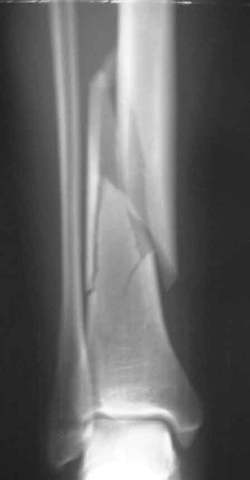

Distale Tibiafraktur mit Weichteilschaden

Die Fraktur reicht bis in das Sprunggelenk